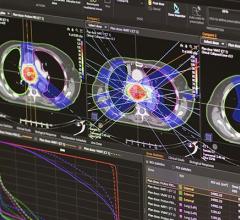

Varian Medical Systems will be exhibiting its complete line of hardware, software, and applicators for HDR and LDR brachytherapy, including the VariSource iX, GammaMedplus iX and the GammaMedplus 3/24 iX HDR afterloaders, the BrachyVision treatment planning system plus the Vitesse module for using transrectal ultrasound (TRUS) images as the basis for a prostate cancer treatment plan. For LDR treatments, the VariSeed treatment planning system is a leading system for this highly specialized form of brachytherapy.